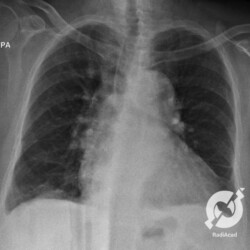

Aumento do volume cardíaco, lesões intersticiais reticulares e obliteração do seio costofrênico direito.